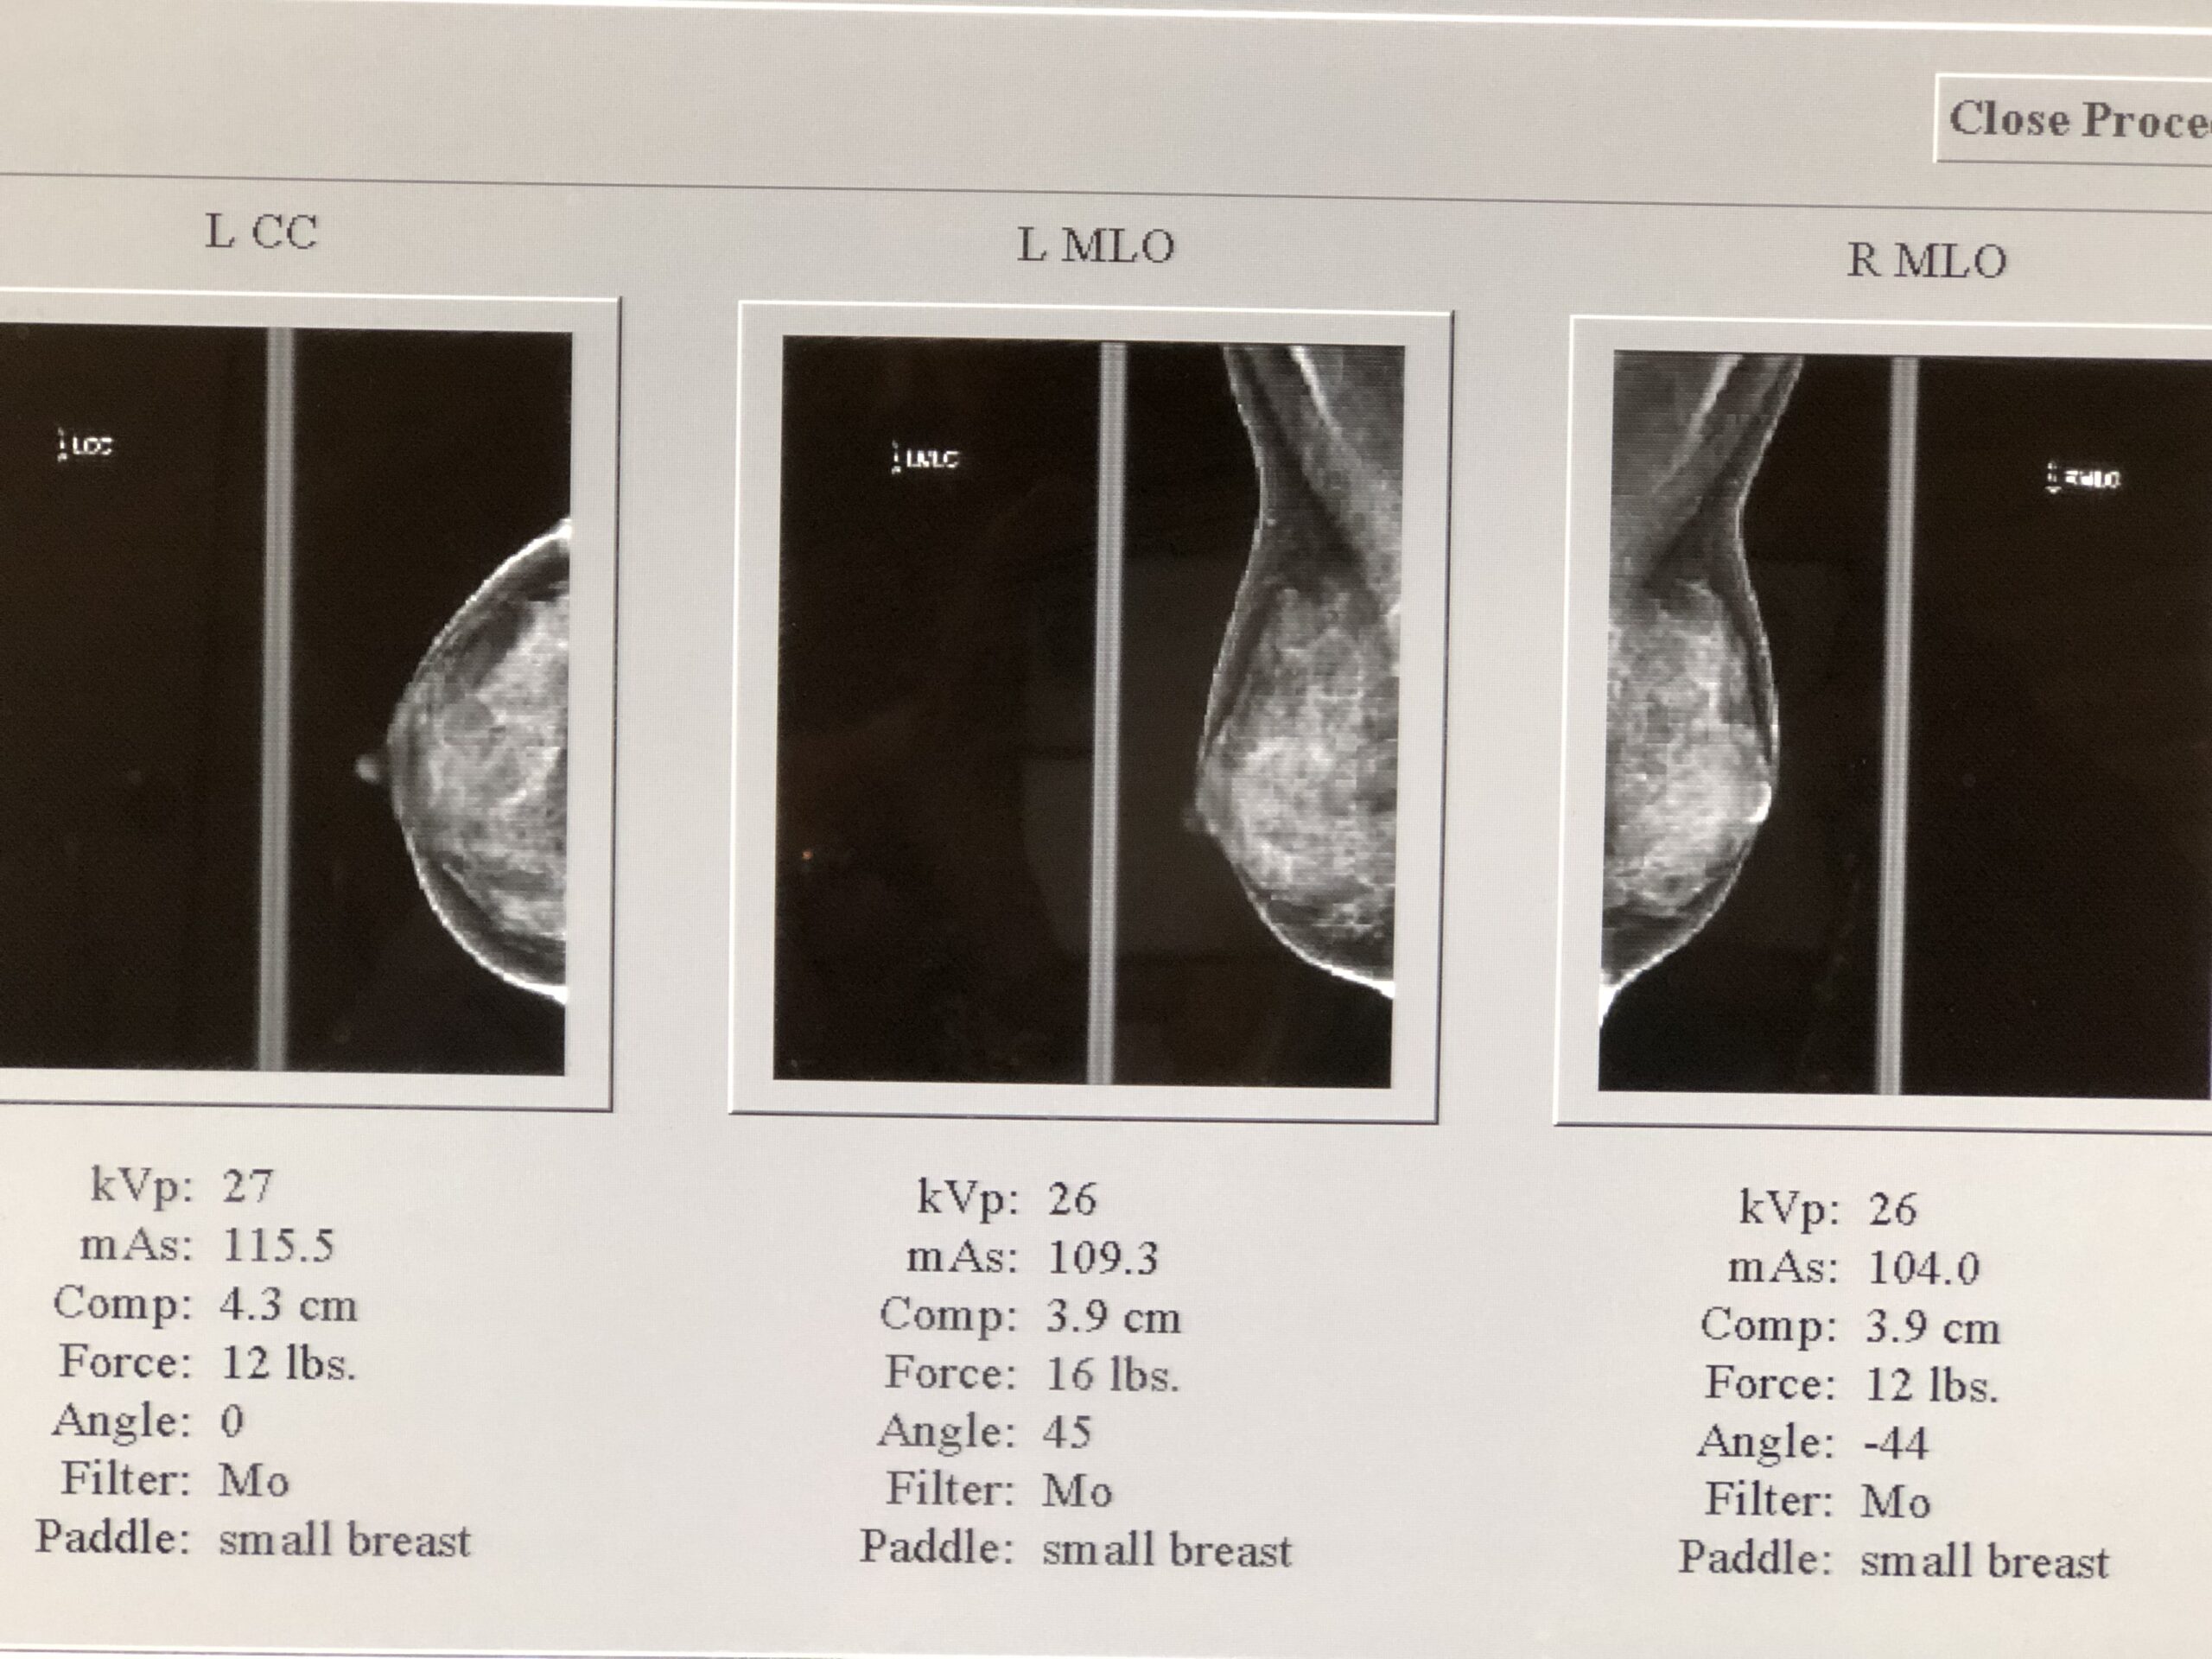

My mammograms with breast implants – the implant is seen as the large white half-dome, and the breast tissue is visualized on top and around the implant

In addition to the standard views, additional implant displacement (ID) views – I call these the “horizon views” (see below) are taken when you have breast implants. The breast tissue is displaced forward off the implant, and is visualized lying overtop of the implant, as seen in my own mammograms, above. The implant is pushed back against the chest wall and the breast is pulled forward over it and then compressed. This allows better imaging of the front part of each breast so the doctor can get a better look at the breast tissue.

Your breast will be positioned into position between the plastic plate and paddle, which are then tightened together to flatten and hold your breast tissue still for imaging. During each view (3 images per breast), you are instructed to hold your breath for around 5 seconds as energy is transferred between the plates to visualize your breast tissue. If you have particularly tender breasts around ovulation or menstruation, then you might want to try to schedule your appointment at a time in your cycle when your breasts are not usually sore or take Tylenol or Ibuprofen an hour before your appointment.